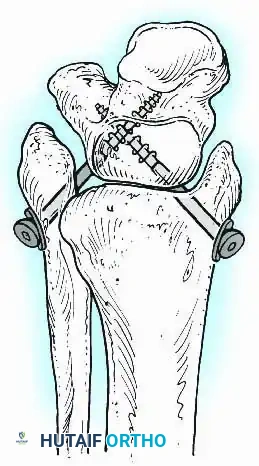

Knee Arthrodesis

While total knee arthroplasty (TKA) is the definitive treatment for knee osteoarthritis, knee arthrodesis remains a critical salvage procedure. The primary indications are a chronically infected TKA that has failed two-stage revision, massive extensor mechanism disruption, severe neuropathic arthropathy, and tumor resection.

Positioning and Technique

The optimal position for knee arthrodesis is 10 to 15 degrees of flexion and 5 to 7 degrees of valgus. This slight flexion assists in foot clearance during the swing phase of gait and makes sitting in confined spaces more manageable. A perfectly straight (0 degrees) knee is cosmetically awkward and functionally detrimental, causing a vaulting gait pattern.